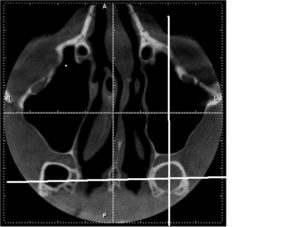

Нередко, особенно при хроническом течении, врачи прибегают к проведению компьютерной томографии. С ее помощью удается послойно оценить строение носа и придаточных его пазух. Главное преимущество этого метода – это возможность определить размер соустий, который влияет на частоту рецидивов заболевания и отражается на тактике лечения.

Единственными методами, которые наверняка могут определить сфеноидит, являются компьютерная томография (КТ) или магнитно-резонансная томография (МРТ) –

- информативнее других методов обнаруживают сфеноидит компьютерная или магнитно-резонансная томография;

КТ — исследование пазухи с помощью рентгеновского излучения. КТ позволяет выявить аномалии синуса, степень поражения слизистой. При исследовании с помощью КТ определяется уровень гноя в пазухе.